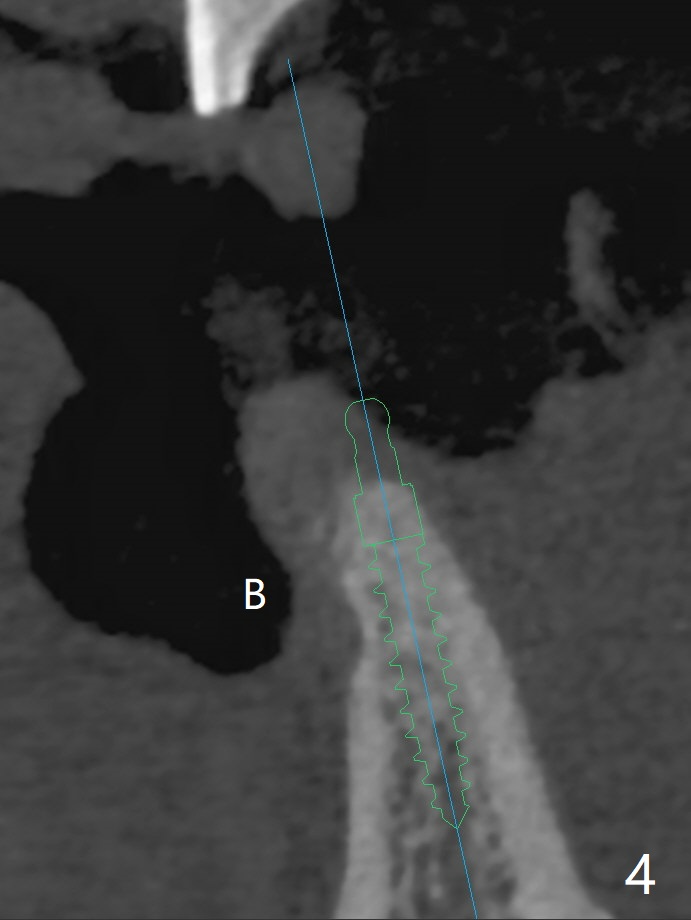

A 38-year-old man has gingival erythema and edema associated with #23-25 bridge (Fig.1). The most abnormal finding is the long pink porcelain at the pontic (Fig.2, 3: P). After taking Alginate for future provisional, the bridge is removed. The edentulous ridge must be atrophic, as shown in low density (Fig.3: *). A 2.0 mm 1-piece implant is proper for the site, as will be shown by CT. In fact 2.5 mm one is proper (Fig.4). The gingival erythema reduces significantly post bridge removal, SRP and water pik. After incision, surgical handpiece and diamond round bur are used to flatten the ridge until 4 mm.